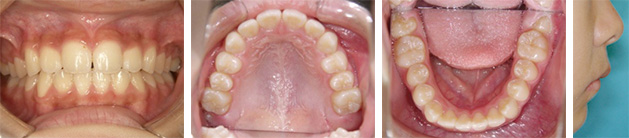

Step4: 生え変わり終了時

Step5:必要によりマルチブラケット法へ

| 術後の経過や現在の様子 | 横顔も問題なく咬合とともに経過良好です。保定装置およびMFTで経過観察しています。 |